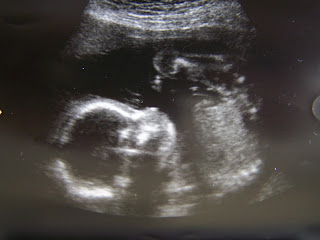

Y ES UNA NIÑA!!!!!!

Por fin nos llamaron, y entramos los tres a la sala donde estaba el ecógrafo. Había dos chicas, les pregunte si podía hacer alguna foto pero no fue posible. Así que empezó el examen... la doctora

iba midiendo y contando que todo estuviera en su sitio. Medidas del cráneo correctas, de las piernas también, riñones, higado, pulmones, unos morritos muy bien formados...todo perfecto, la medida de la cintura un poco por encima de la media...jejejejeje ¡¡¡¡¡¡anda mira como el padre!!!!!.

Solo cuando ya había terminado el examen y va y dice la doctora: "bueno, pues ya está, esta todo bien, ¿tenéis alguna pregunta mas?", pero vamos a ver!!!!, yo tengo LA PREGUNTA!!!!, sino a que hemos venido aquí??? ¿it's a boy or it's a girl?? (por lo visto si los padres no preguntan no dicen nada, por si acaso los padres no quieren saberlo).  Pues vamos a verlo, colocó el ecógrafo por

debajo del culete, y como le dije a Marivi: "hay no se ve pichulin". Cosa que confirmo la doctora cuando dijo que "probablemente era una niña", que nunca se puede saber al 100% pero que casi con total seguridad es una niña. A Viki la sonrisa no le cabía en la cara, y tengo que d

Cuando salimos estábamos los tres radiantes de alegría, teníamos la lágrima a punto de saltar de alegría. Recogimos las fotos y empezó el carrusel de llamadas y mensajes...ES UNA NIÑA!!!!

1. Aqui estamos la tita Charo y yo viendo las primeras fotos reales de nuestra niña Raquelita y....es PRECIOSA!! que carita de bebita regordeta y pepona..la veo, es preciosa ...Ay por Dios tita Charet que largo se nos va a hacer esto!!!!!!